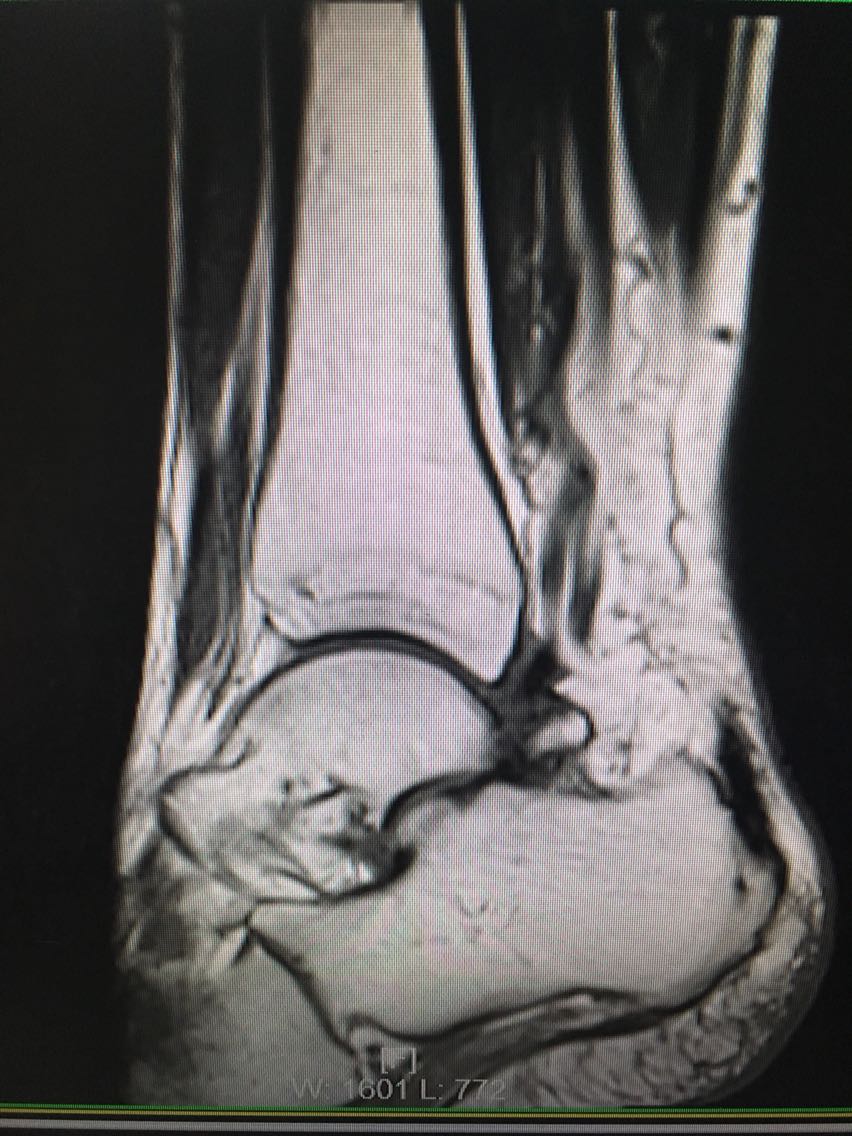

主诉:反复右侧踝关节扭伤3年余。 病史:患者F/60,自述3年前扭伤右足踝,未予以重视及治疗,后反复出现右侧踝关节扭伤,目前自觉右踝松弛,不能做剧烈运动,局部无明显疼痛。

查体:右踝关节踝前抽屉试验和内翻试验阳性,局部无压痛。 辅查:MRI检查如下